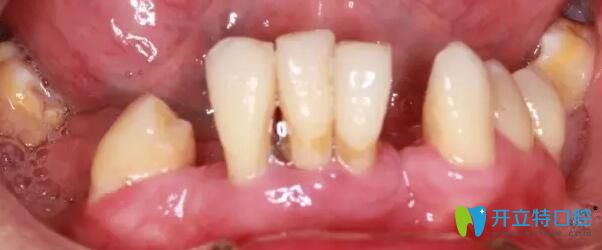

南通摩爾口腔牙齒種植前

(圖一)術(shù)前患者口腔狀況圖